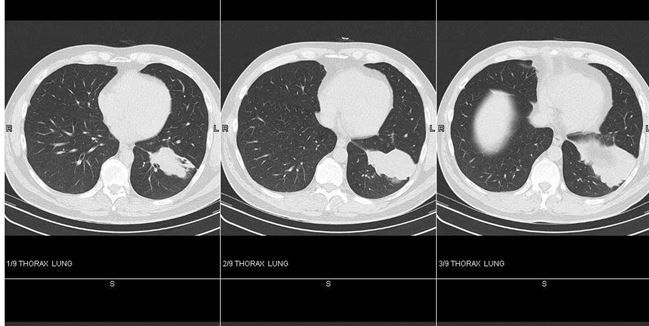

A 57-year-old man comes to see you complaining of fevers, chills, and left-sided back pain of a week’s duration. A chest x-ray film shows a dense left-sided infiltrate, and you make a presumptive diagnosis of left lower lobe (LLL) community-acquired pneumonia. You treat him with moxifloxacin 400 mg for 10 days, but after initial improvement in symptoms of fever, chills, and malaise, his back pain persists. A repeated chest x-ray film 1 month later shows persistence of the infiltrate, and you send the patient for a CT scan of the chest. Representative images are shown at right in Figure 1 (top-sagital section), Figure 2 (center-coronoal section), and Figure 3 (bottom-coronal and sagital section, mediastinal view). (Click images to enlarge.)

Note that the arrows in the last 2 frames of Figure 3 (bottom) point to mediastinal adenopathy. A PET/CT scan shows uptake of tracer consistent with malignancy in both the LLL mass and the mediastinal nodes.